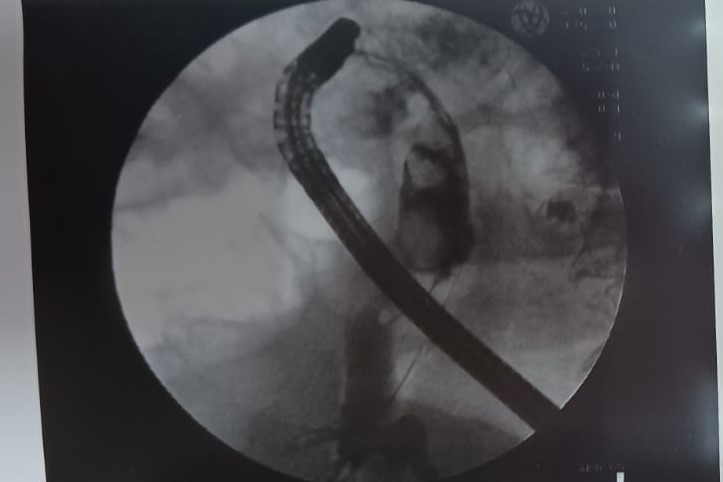

Бригада медиков провела операцию в два этапа. Сначала был обеспечен доступ к желчным протокам, затем с помощью холедохоскопа SpyGlass проведена холангиоскопия и выполнена контактная лазерная литотрипсия конкрементов с удалением осколков.

Контрольное исследование подтвердило, что желчный проток полностью очищен от камней. Пациентку выписали из стационара в удовлетворительном состоянии уже через неделю после операции.

Добавим, что SpyGlass (дословно «подзорная труба») — это ультратонкий эндоскоп, который проводится в желчные протоки через канал операционного дуоденоскопа, введённого в просвет двенадцатиперстной кишки. Технология обеспечивает прямой визуальный контроль, превращая диагностику в лечебную процедуру. Врач видит желчные протоки изнутри в высоком качестве, далее также под визуальным контролем крупные камни дробятся лазером на мелкие фрагменты, которые извлекаются наружу. Визуализация просвета желчных протоков позволяет также прицельно забирать образцы тканей для исследования при подозрении на опухоль.